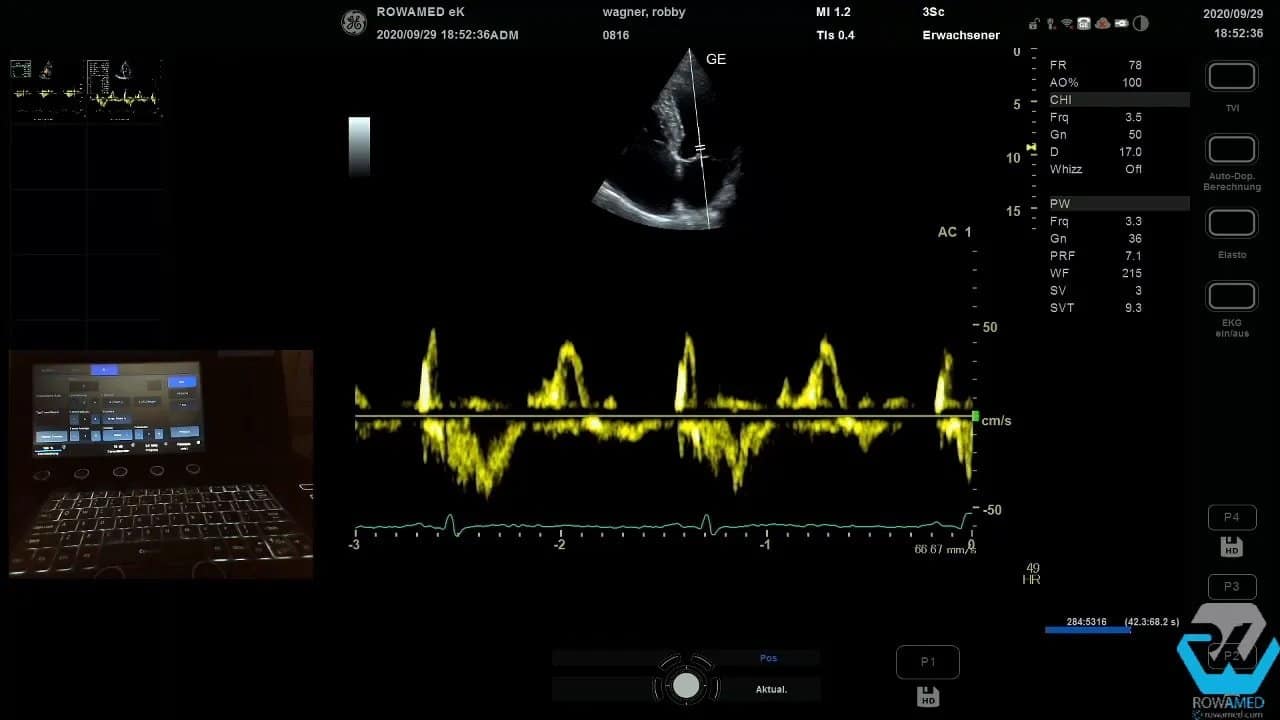

Step 10: Das Mitraleinstromprofil und die diastolische Funktion beurteilen

Die diastolische Funktion ist ein klassischer Bestandteil der Transthorakale Echokardiographie. Zunächst leiten Sie über den transmitralen Einstrom das E- und A-Wellen-Profil ab. Dafür wird im Messmenü auf die Mitralklappe umgestellt und dann die E-Welle, deren Dezelerationszeit sowie die A-Welle vermessen.

Technisch klappt das nicht immer beim ersten Versuch. Das ist kein Drama. Entscheidend ist, ruhig zu bleiben, das Messmenü korrekt zu wählen und die Kurve erneut sauber aufzunehmen. Im Beispiel ergab sich schließlich ein E/A-Verhältnis von 0,9, also ein unauffälliger Befund.

Für die weitere Einordnung einer möglichen diastolischen Dysfunktion wird anschließend der Gewebedoppler am medialen Mitralklappenanulus verwendet. Dort messen Sie das E‘. Aus E und E‘ lässt sich das Verhältnis E/E‘ berechnen. Dieses hilft bei der Abschätzung linksventrikulärer Füllungsdrücke.